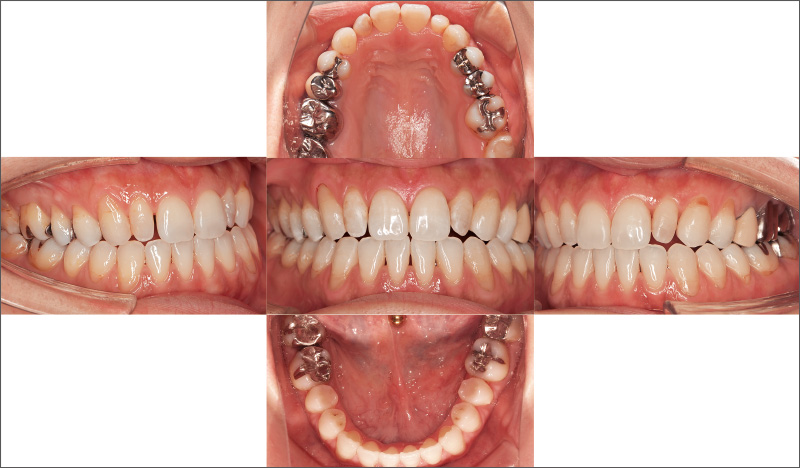

症例3-2 叢生の改善に加え、咬合の安定を得ることができた。表層だけでなく、深層までしっかり診て判断し、対応することが大切である。

安定した口腔内を保つ30代女性。前歯の叢生と左右非対称であることが気になり、「iGo」での治療を希望。₅ ₅が舌側傾斜する鞍状歯列弓で、₆₅ ₅₆の咬頭嵌合位での咬合が確立されておらず、将来的に咬合が理由で前歯にトラブルが起こる可能性があることから、咬合再構成を提案しました。歯科における一般開業医の役割は、患者さんの口腔内が安定し、10年後、20年後も歯を失わずにいられる方法を考えることです。主訴だけでなく、口腔内の長期安定のため咬合までしっかりと診て適切なコンサルテーションを行い、治療につなげていくことが重要です。

「iGo」を導入するメリットは、歯列を補正し、咬合を改善することで、手間と費用をかけて装着した補綴装置が長く維持できるようになること。そうした治療の価値を発信することで患者さんのデンタルIQを高め、「そうした治療を受けたい」と自発的に人が集まってくるようなクリニックになれば、自費診療の提案も行いやすく、経営の安定化も図れますし、それがひいては日本の歯科レベルの底上げにもつながるではないかと考えています。